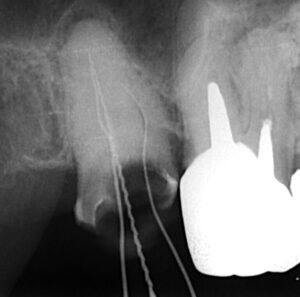

ファイルという根っこの治療に使う器具を入れて

レントゲン撮影をします。

このように細いですが3本の根管(根っこの管)が見つかりました。

最初のレントゲンでは真ん中に白いもの(根管充填材)が

少し写っているだけです。